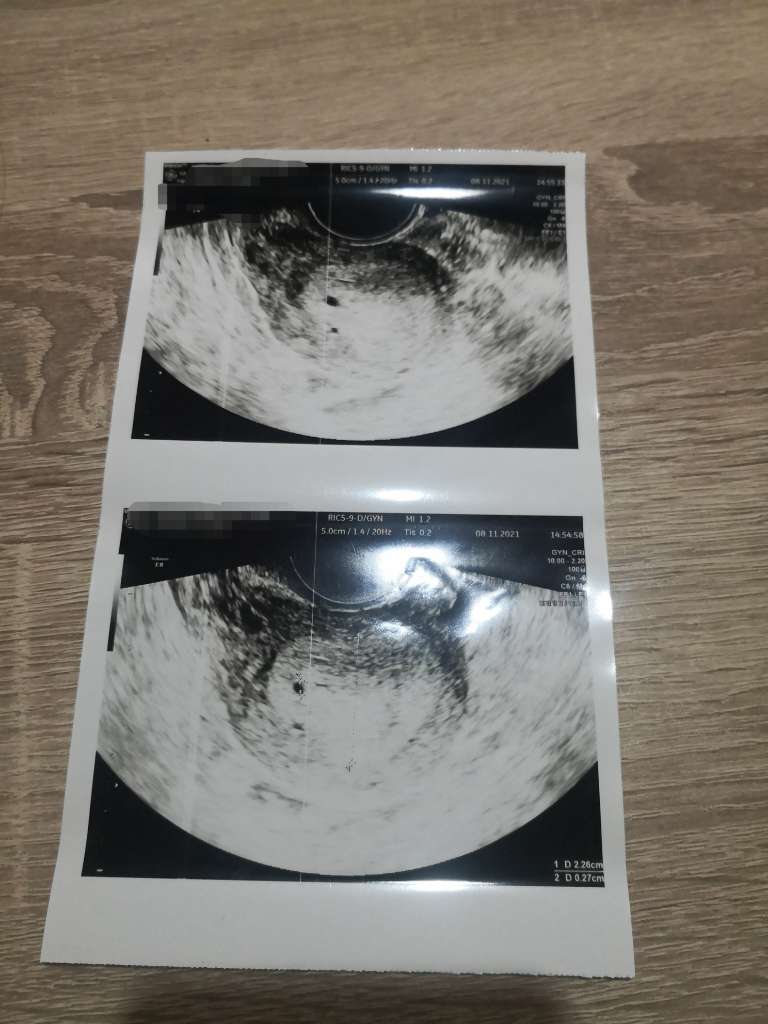

Miałam podobną sytuację. Lekarz też widział pęcherzyk, ale nie był na 100% pewien, bo nic się kupy nie trzymało (termin miesiączki i negatywny test ciążowy). Kazał zrobić betę - negatywna. Powiedział, że najprawdopodobniej przyjdzie krwawienie i po nim mam przyjść zobaczyć czy coś jest widoczne. Okres przyszedł o czasie, na następnej wizycie po okresie czyściutko i najprawdopodobniej był to jakiś skrzepik. Załączam usg tego udawanego pęcherzyka 😉

Załączniki

• 707cad65-3d78-4756-9360-ff57f969fdbd.jpg